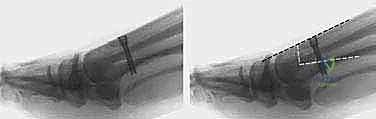

في العاصمة اليمنية صنعاء، يبرز اسم الأستاذ الدكتور محمد هطيف كعلامة فارقة والمرجع الطبي الأول في جراحة العظام والمفاصل وتصحيح تشوهات القدم والكاحل. يقدم الدكتور هطيف، متسلحاً بخبرة تتجاوز العقدين من الزمان، حلاً جراحياً ثورياً ومتقناً يُعرف باسم جراحة شفرون ثنائية المستوى لقطع العظم (Biplanar Distal Chevron Osteotomy). هذه التقنية الجراحية الدقيقة لا تكتفي بتصحيح الانحراف العادي، بل تعالج التشوهات المتوسطة والمتقدمة التي تتسم بزيادة معقدة في الزاوية المفصلية المشطية البعيدة (DMAA)، مما يعيد للقدم وظيفتها الميكانيكية الطبيعية وشكلها السليم.

- الريادة في جراحات القدم والكاحل: يُعد من الرواد القلائل الذين يتقنون تقنية "شفرون ثنائية المستوى" المعقدة، والتي تتطلب حساً هندسياً دقيقاً ومهارة يدوية فائقة لضمان عدم عودة التشوه.

* الزاوية المفصلية المشطية البعيدة (DMAA): في الحالات المتقدمة، يتشوه سطح المفصل نفسه ويميل بزاوية غير طبيعية. الجراحات التقليدية تفشل في علاج هذه الزاوية، وهنا تبرز أهمية تقنية شفرون ثنائية المستوى التي يطبقها الدكتور هطيف لتصحيح هذه الزاوية بدقة متناهية.